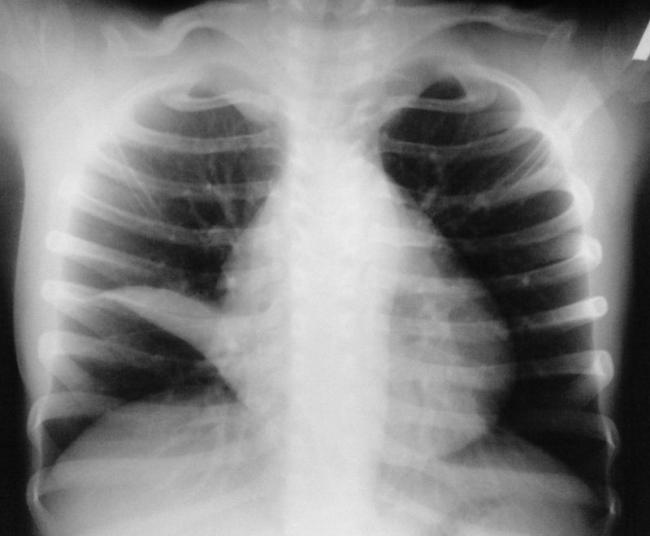

На рентгеновских снимках выявляют следующие признаки, указывающие на спадение легочной ткани:

Однородное затемнение в области поражения. Размеры тени зависят от вида ателектаза: при долевом выявляется обширное затемнение, при сегментарном — в виде клина или треугольника, расположенного вершиной к корню легкого, дольковые ателектазы множественные и похожи на очаговую пневмонию. Дистензионный ателектаз расположен низко, около диафрагмы, имеет небольшие размеры и вид поперечных полос или темных дисков. Смещение органов: при компрессионном ателектазе смещение наблюдается в здоровую сторону, так как на стороне поражения давление больше, при обтурационном, наоборот – смещение будет в сторону ателектаза, так как на стороне поражения нарастает притягивающее отрицательное давление. Подъем купола диафрагмы – это видно по расположению печени.

Помимо всего перечисленного выше, рентгеноскопия, то есть исследование «вживую», позволяет увидеть куда смещаются органы в зависимости от фазы дыхания, кашля. Это является дополнительным признаком ателектаза, помогающим выявить тип болезни.